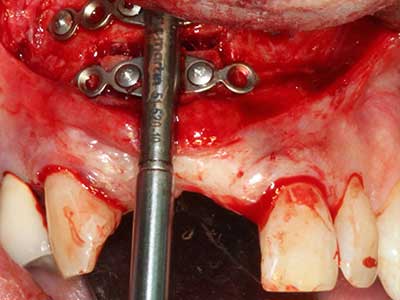

Il tessuto osseo non è semplicemente una struttura minerale, ma contiene anche una percentuale significativa di fibre di collagene. Ciò significa che non possiede solo una buona forza di compressione, ma anche un certo livello di flessibilità che è possibile sfruttare durante l'esecuzione degli accrescimenti di osso. Nella procedura di espansione classica con incisione ossea, la cresta alveolare atrofizzata viene incisa longitudinalmente ed espansa con cautela dopo aver raggiunto una profondità di osteotomia adeguata (figg. 13-16), idealmente senza una sostanziale rimozione del periostio (Brugnami, Caiazzo et al. 2014, Stricker, Fleiner et al. 2014). I sistemi a piastra e vite con distanza di espansione incrementale si sono dimostrati efficaci nella separazione delle due lamelle ossee restando al di sotto della soglia di frattura. In generale, sono richieste larghezze dell'osso residuo di almeno 3-4 mm (Chiapasco, Zaniboni et al. 2006) per garantire un'adeguata flessibilità e una copertura sufficiente dell'osso per gli impianti futuri. Se necessario, un'osteotomia di rilascio verticale su uno o più lati può migliorare la flessibilità. Una combinazione con ulteriori tecniche di accrescimento, in particolare dal lato buccale, è stata descritta come un'alternativa alla tecnica classica.

La procedura di incisione è particolarmente atraumatica e non comporta una perdita significativa di dimensione durante l'utilizzo delle seghe piezoelettriche, così come non si notano differenze rilevanti tra impianti in mandibole incise e impianti in una cresta alveolare senza deficit osseo (Chiapasco, Zaniboni et al. 2006, Danza, Guidi et al. 2009). Una sufficiente irrigazione continua è essenziale, tuttavia, in particolare con incisione profonda e localmente ristretta, per prevenire la sollecitazione termica nelle regioni apicali dell'osteotomia.